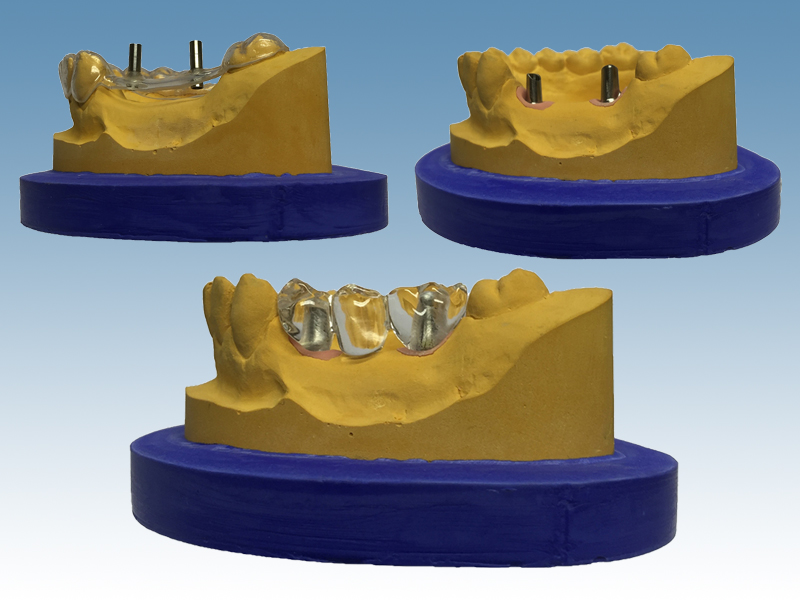

Individuelle Abutments für Implantate

Und weil die zu ersetzenden Zähne nicht frei darüber schweben können, braucht es noch individuelle Stützpfeiler (engl. Abutments).

Im Normalfall sind Abutments aus Titan, Aluminiumoxidkeramik oder aus Zirkondioxidkeramik. Sie werden bei uns in enger Absprache mit dem Behandler im CAD/CAM-Verfahren nach der idividuellen Situation des jeweiligen Patienten

Unterbau für Einzelkronen oder Brücken, aber auch zur Fixierung von herausnehmbaren Zahnersatz

Abutments kommen zum Einsatz bei

- Einzelkronen ohne die Notwendigkeit, Nachbarzähne zu beschleifen

- größeren Konstruktionen, für die nicht mehr genügend Zähne als Stützen vorhanden sind

- Herausnehmbare Prothesen, für die damit eine stabilere Lage im Mund geschaffen werden kann